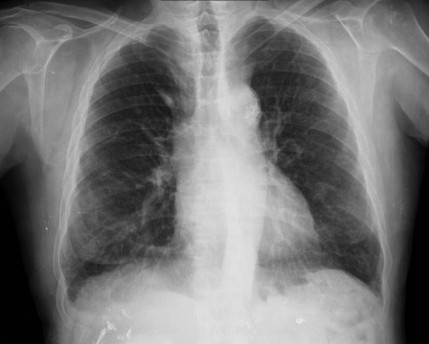

CASO: Febrícula y tos de 4 días de evolución.

Hallazgos:

- En la placa PA se observa una asimetría en los hilios pulmonares, el hilio izquierdo tiene una densidad aumentada.

- Tras examinar la placa lateral se observa un aumento de densidad en la columna que puede ser compatible con una condensación, es el signo de la desnificación vertebral.

SIGNO DE LA DENSIFICACIÓN VERTEBRAL: En la radiografía lateral normal, la densidad de la columna torácica tiende a disminuir desde la parte superior hasta el diafragma; la alteración de ese patrón por la presencia de una densidad superpuesta a la columna, indica la existencia de una consolidación pulmonar. Este signo adquiere especial valor cuando en la proyección posteroanterior la consolidación está oculta en el espacio retrocardíaco o en la base pulmonar.